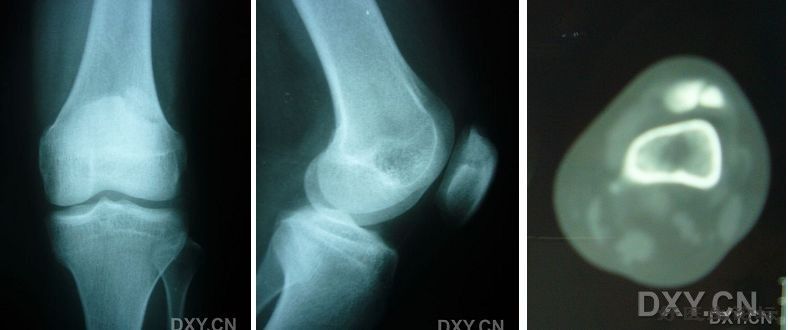

影像学检查

X线摄片

a、常规三个位置 1、正位(前后位) 2、侧位 3、髌股关节轴心位

b、髁间窝位或隧道位 屈膝40°~50°后前位 股骨髁骨软骨炎

c、站立 (负重)位 – 骨关节炎

* CT

* MRI

MRI